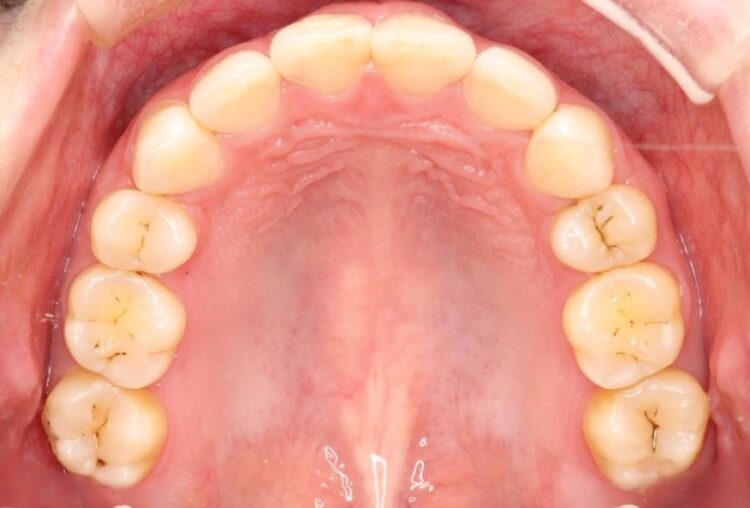

治療費の安い矯正治療を希望されていたため、メタルのワイヤー装置にて治療する計画にしました。また、歯みがきが苦手だったため、矯正治療をする前に徹底的にブラッシング指導を行いました。

出ている歯を引っ込めるためのスペースを作るため、上下左右の小臼歯を抜歯し、ワイヤー矯正を行いました。治療後は、口元がスッキリとしたことで患者様にも喜んでいいただきました。